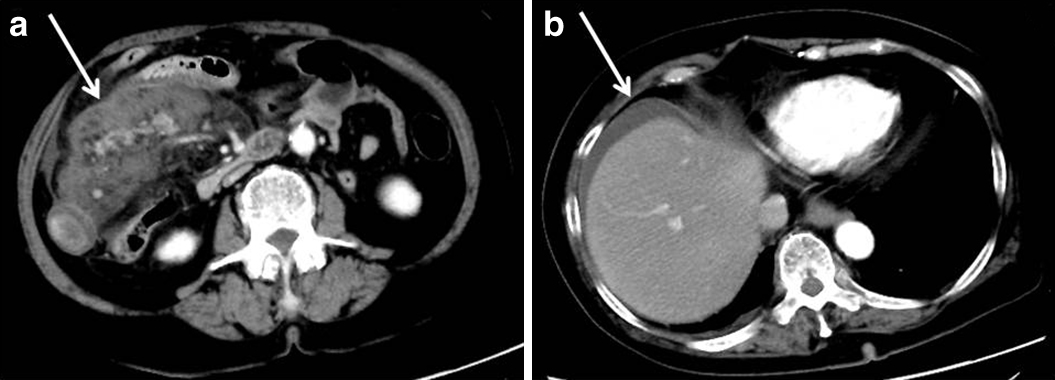

入院時腹部単純CT所見:左腎下極付近の腸間膜脂肪織に濃度上昇を認めたが,膵臓との連続性は見られなかった(Fig. 1).腹水,free airは見られなかった.

CT scan upon admission revealed mesenteric edema below the left kidney (a) without continuity to the normal pancreas (b).